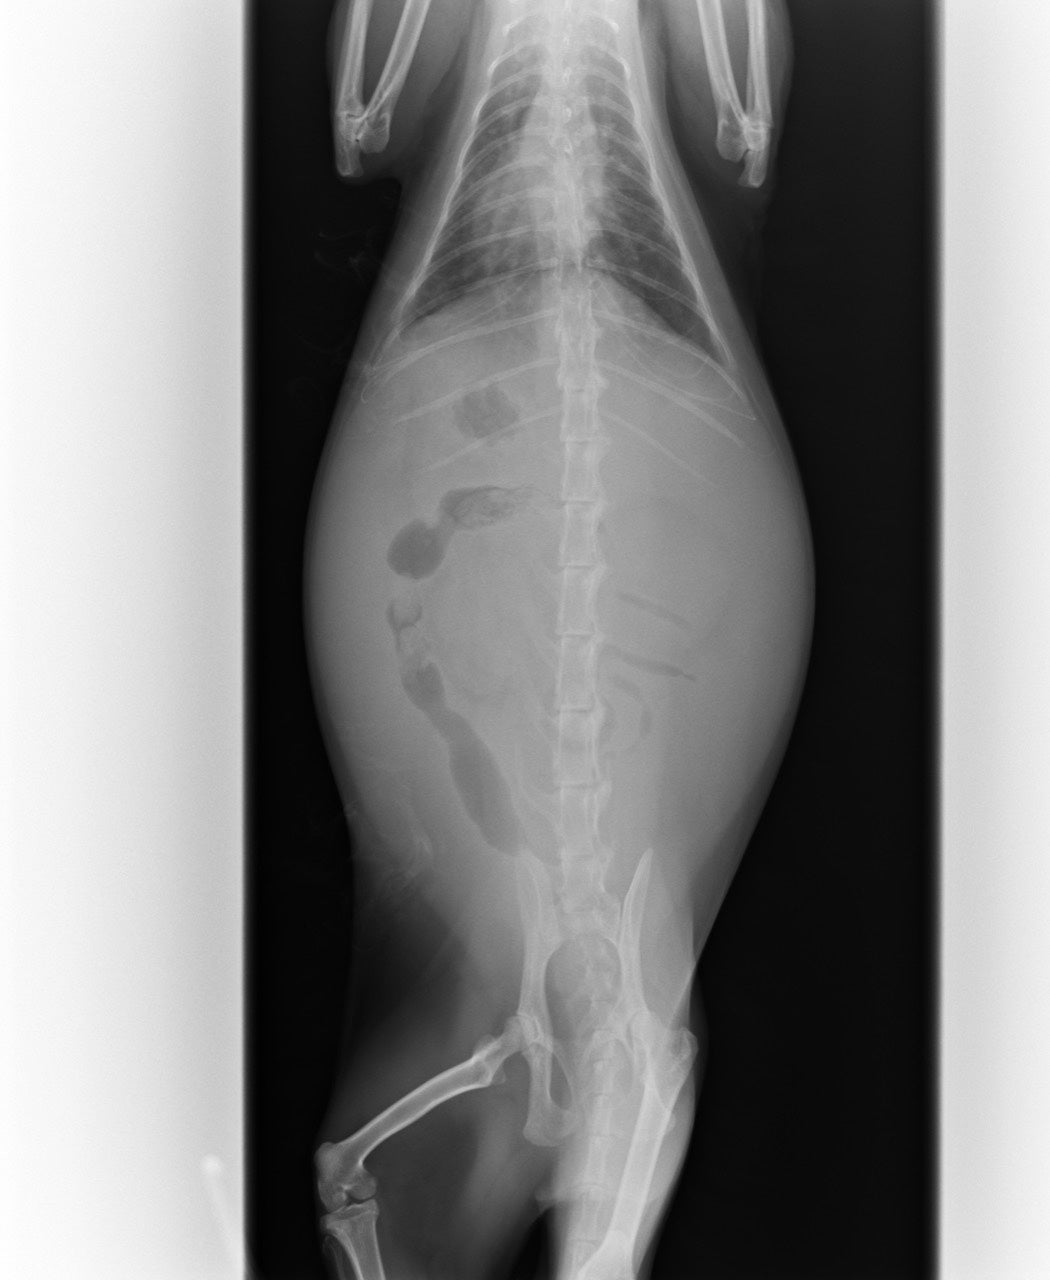

沢山の腹水がたまっており、PCR検査をしました。

腹水の量と色、超音波、血液検査の結果でFIP暫定診断となりました。

腹水だけではなく肉芽腫もあることがわかり、

ウェットタイプとドライタイプの混合で、中期FIPと診断されました。